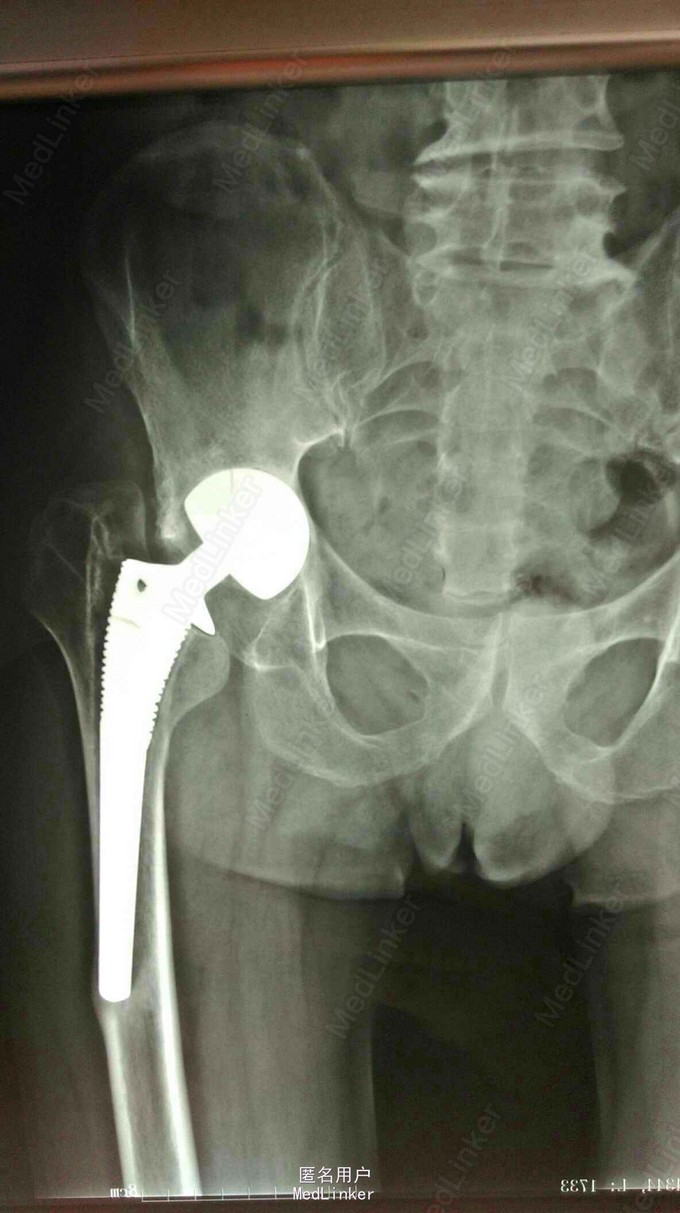

髋关节置换术后15年,疼痛2年。 15年前左股骨头坏死,在外院行股骨头置换术,2年前左下肢短缩,左髋关节疼痛,活动受限。

左下肢短缩4cm,左髋关节外展受限,叩痛阳性,左下肢血运,感觉正常。

左股骨头置换术后假体松动 完善术前检测后行髋关节翻修术,术中髋臼侧打压植骨,术后左下肢短缩1cm ,顺利出院。

年轻患者第一次置换还是应该全髋关节置换